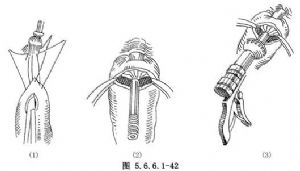

⑤去掉贲门残端的Kocher钳,用吸引器吸尽胃内容物。用一把弯血管钳经贲门口插至胃腔内[图5.6.6.1-42(1)],再从胃底拟定吻合部位作孔穿出并夹住中心杆后从胃底作孔处进入胃腔,之后再经贲门口拉出胃腔外,使胃底与食管残端靠拢,结扎上述三针缝线[图5.6.6.1-42(2)]。

⑥将中心杆插至吻合器主体内,扭紧固定螺母,打开保险钮,握压手柄,进行食管胃订合[图5.6.6.1-42(3),5.6.6.1-43(1)]。